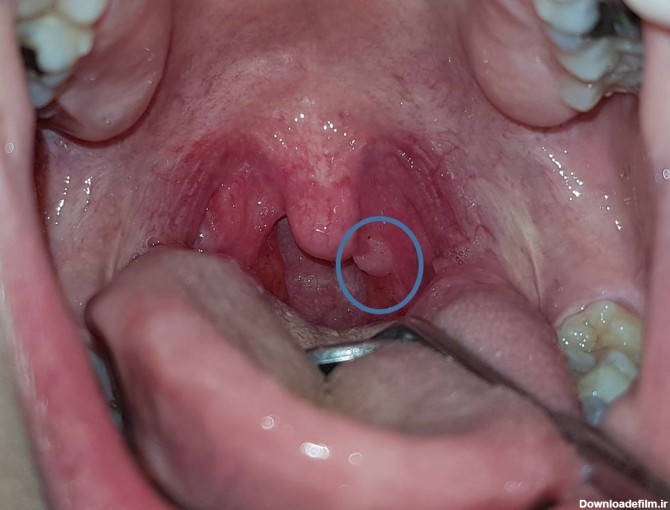

عکس زگیل در سقف دهان

زگیل دهانی نوعی زگیل تناسلی در داخل دهان می باشد که از طریق اورال سکس یا رابطه دهانی منتقل شده و می تواند منجر به سرطان دهان و حلق در فرد شود.

ویروس پاپیلومای انسانی میتواند نواحی مختلف بدن مانند دهان، گلو و دستگاه تناسلی را آلوده کرده و باعث ایجاد زگیل شود. در این پست با زگیل دهانی آشنا میشوید!